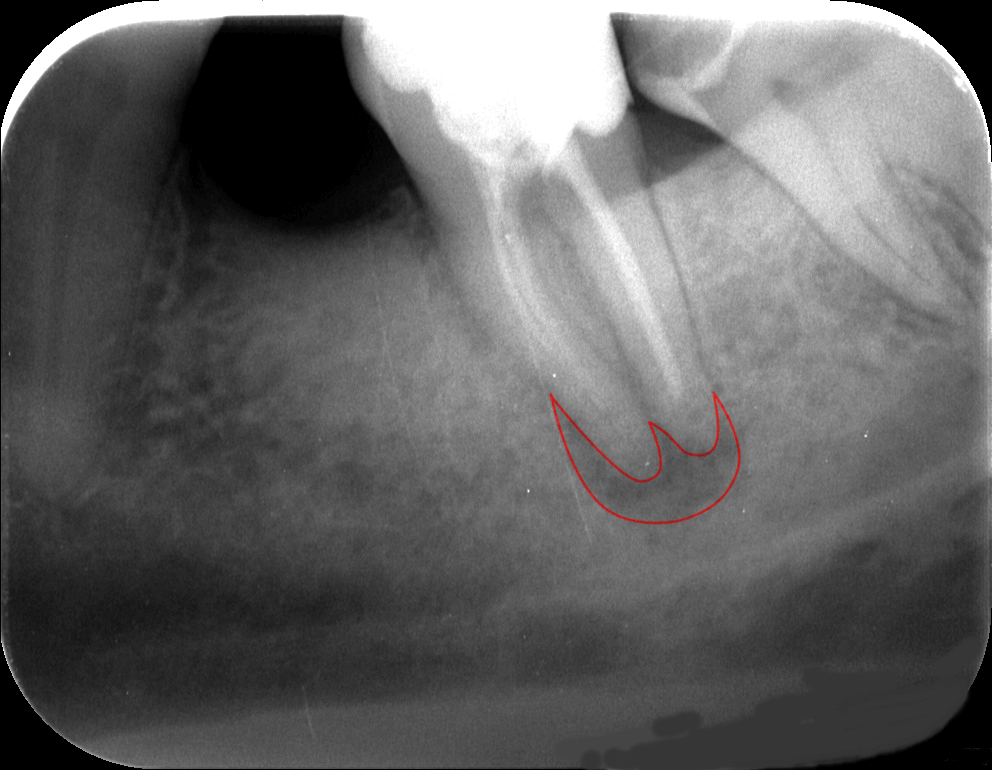

A diagnózis felállításához is elengedhetetlenek a felvételek. A csontállományban megjelenő fekete foltok (az alábbi képen pirossal bekarikázva) például gyulladásról árulkodnak, és a kiterjedt, a fogbélt is elérő szuvasodással párosulva igen gyakran ez teszi szükségessé a gyökérkezelést.